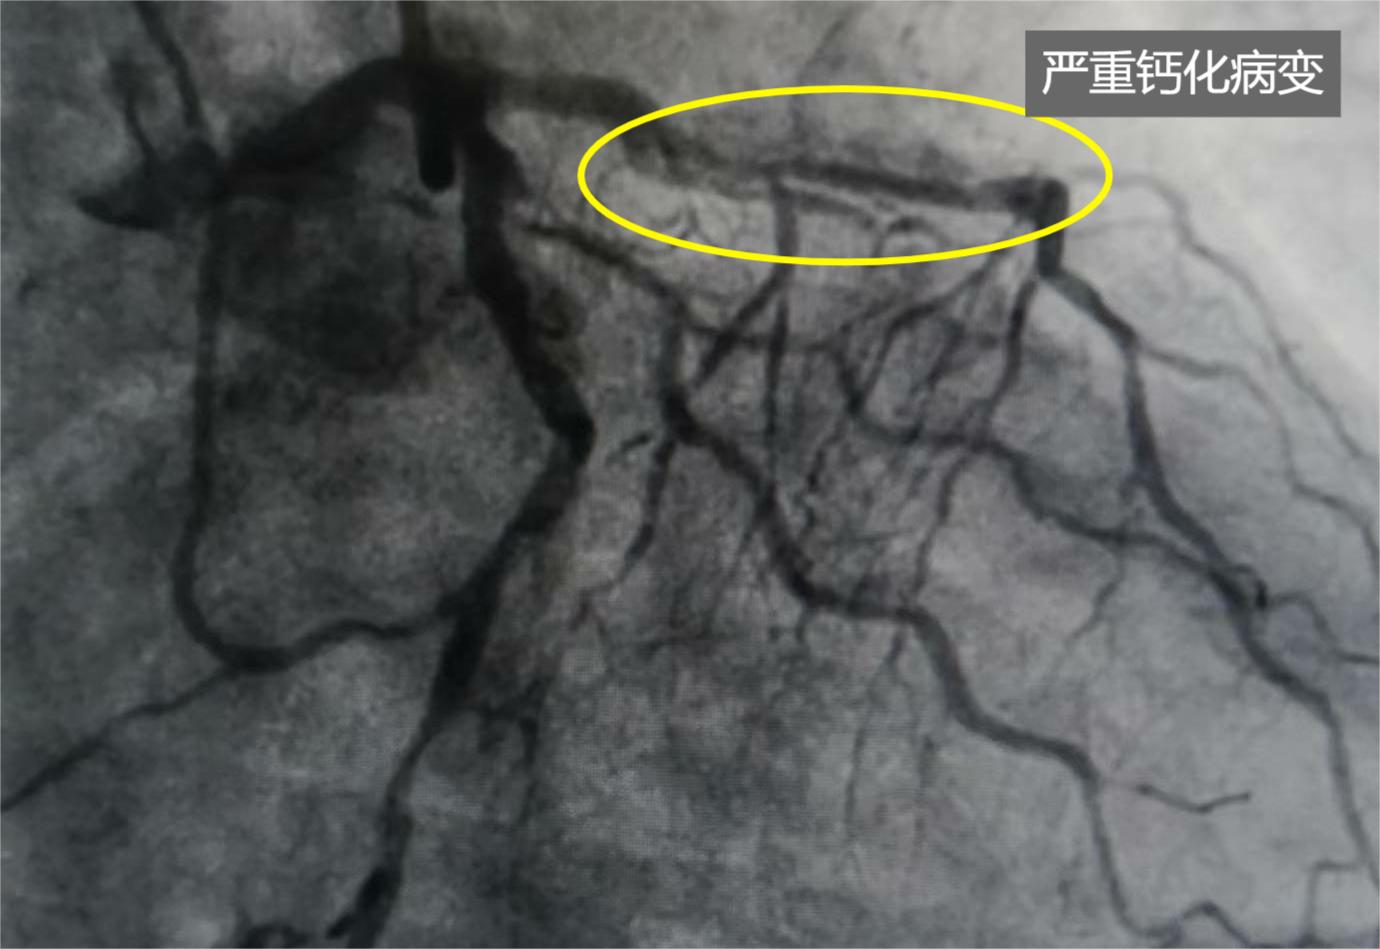

馬老先生術前的前降支鈣化造影。

5月6日中午,歷經兩個多小時的手術,在衡水市人民醫院(哈勵遜國際和平醫院)心內科負責人張慧晶指導下,副主任醫師肖建東博士利用精湛技術操控旋磨導絲及旋磨頭,對馬老先生前降支鈣化病變進行了“冠狀動脈內旋磨術”處理:在面積僅有7平方毫米左右的心臟血管里,用微導管輔助交換旋磨導絲至心臟前降支遠端,用一枚直徑1.75毫米的旋磨頭,以每分鐘16萬轉的速度高速旋磨,將重度鈣化病變處一點點磨掉,然后再用球囊充分擴張前降支病變處,并成功植入兩個支架,打通了馬老先生的“生命通道”。在推出手術室后,馬老先生用舒展的笑容,表達了此刻滿滿的幸福。

就在5月3日上午,馬老先生因胸痛、伴惡心被家人緊急送到哈院就醫,張慧晶接診了患者,考慮心絞痛復發。追問病史,獲知患者于2019年11月14日曾在哈院進行冠脈造影檢查:前降支鈣化,近段彌漫狹窄80%至90%;回旋支彌漫狹窄70%;右冠開口局限狹窄70%。當時因冠脈旋磨技術在哈院開展較少,醫生建議患者進行冠脈搭橋手術,但患者當時不想進行搭橋手術,一直拖到現在。